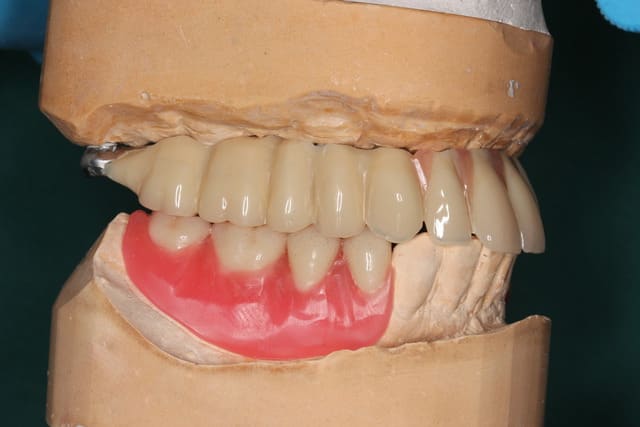

Ben des études statistiques moi j en ai pas... J ai que mes propres cas

Par contre je peux te dire que les 4 plaques et même le monodisk sont sonores et parfaitement indolores donc a priori intégrés béton

Sûr par contre que j aurais pas obtenu le même résultat avec cette vieille merde d interpore ( que je suspecte perso d être responsable de bcp d échecs sur des disks et plaques )

Manque que 6 e.max en antérieur !